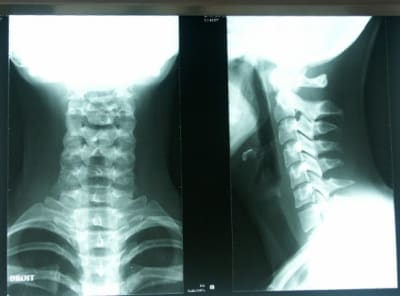

Je vous livre le compte rendu fait par le radiologue sur le télérachis:

- pas de bascule pelvienne.

- pas de déviation scoliotique.

- hyperlordose lombaire significative.

- pas de spondylolyse.

- on note une petite surcharge au niveau des articulations postérieures en L5-S1 liée à l'hyperlordose lombaire.

Sur cervicales:je considère que la posture n'est pas au top,mais bon...